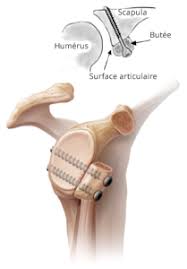

- La butée de Latarjet peut être réalisée à ciel ouvert ou sous caméra (mais pas par moi)

- La stabilisation capsulaire +/- associée à un remplissage de l’encoche